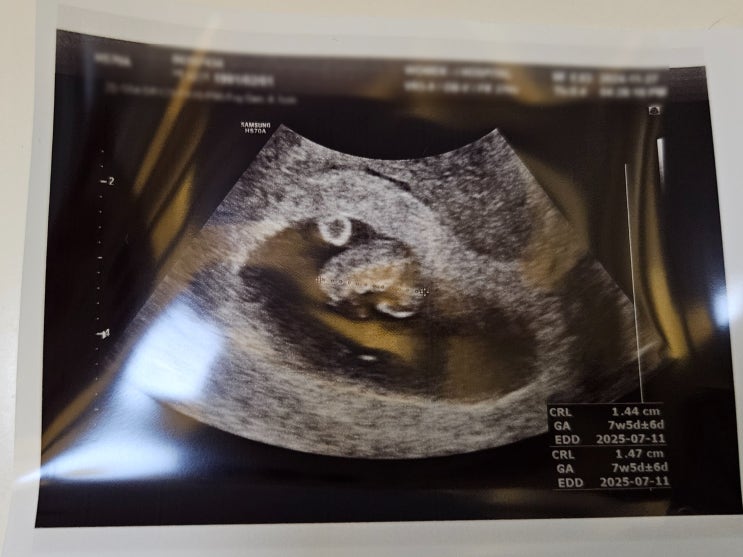

임신 5주차 6주차 7주차 아기집/입덧/초음파/심장소리

5주차 아기집 확인. 사실 막생 기준으로는 4주 5일차. 5주차부터 속 쓰리고 울렁거리기 시작했다. 듣던 것...